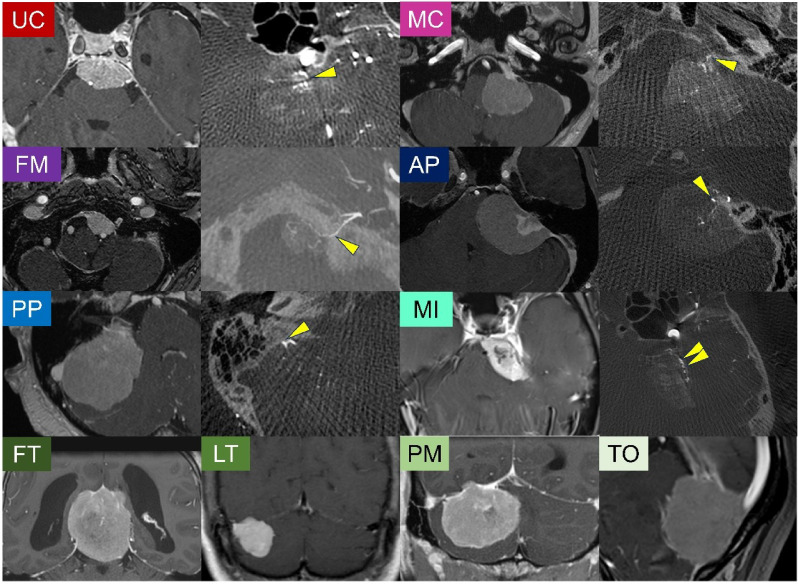

脑膜瘤的解剖定位越来越多地与它们的遗传改变联系在一起。然而,专门针对后窝脑膜瘤的基因组景观和临床意义的研究仍然有限。在这项研究中,我们研究了后窝脑膜瘤的遗传、解剖和临床特征,旨在阐明遗传改变、肿瘤精确定位和预后之间的关系。对132个连续的肿瘤进行全外显子组测序,以确定驱动突变和拷贝数改变(CNAs)。根据硬脑膜附着、动脉供应和术中发现仔细评估肿瘤定位。根据驱动突变和CNAs,将肿瘤分为3个分子组:A组(无Merlin通路改变,n = 71 (54%)), B组(NF2突变/22q丢失,无高危CNAs, n = 45(34%))和C组(高危CNAs, n = 16(12%))。值得注意的是,C组表现出强烈的解剖偏好,81%来自中线结构,包括内侧切牙和斜坡。C组肿瘤与大体全切除后较差的无进展生存率显著相关(P = 0.023),即使在解剖学上仅限于位于内侧切牙和斜坡的肿瘤时(P = 0.0003),这一点仍然显著。在多变量分析中,C组(P = 0.020, HR 6.60)和术前肿瘤体积bbb10 cc (P = 0.044, HR 9.41)独立预测预后不良。总的来说,结果表明大约10%的后窝脑膜瘤含有高危CNAs,主要位于中线位置,并且与较差的临床结果相关。除了识别驱动突变外,CNA谱分析可能为后窝脑膜瘤的风险分层和辅助治疗决策提供有价值的工具。

Anatomical localization of meningiomas has been increasingly linked to their genetic alterations. However, studies focusing specifically on the genomic landscape and clinical implications of posterior fossa meningiomas remain limited. In this study, we investigated the genetic, anatomical, and clinical characteristics of posterior fossa meningiomas, aiming to clarify the association between genetic alterations, precise tumor localization, and prognosis. Whole-exome sequencing was performed on 132 consecutive tumors to identify driver mutations and copy number alterations (CNAs). Tumor localization was carefully assessed based on dural attachment, arterial supply, and intraoperative findings. Based on driver mutations and CNAs, tumors were classified into three molecular groups: Group A (no Merlin pathway alterations, n = 71 (54%)), Group B (NF2 mutation/22q loss without high-risk CNAs, n = 45 (34%)), and Group C (high-risk CNAs, n = 16 (12%)). Notably, Group C showed a strong anatomical predilection, with 81% arising from midline structures, including the medial incisura and clivus. Group C tumors were significantly associated with poor progression-free survival following gross total resection (P = 0.023), and this remained significant even when the analysis was anatomically restricted to tumors located in the medial incisura and clivus (P = 0.0003). In multivariable analysis, Group C (P = 0.020, HR 6.60) and preoperative tumor volume > 10 cc (P = 0.044, HR 9.41) independently predicted poor prognosis. Overall, the results demonstrated that approximately 10% of posterior fossa meningiomas harbored high-risk CNAs, predominantly in midline locations, and were associated with worse clinical outcomes. CNA profiling in addition to the identification of driver mutations may provide a valuable tool for risk stratification and decision-making regarding adjuvant therapy in posterior fossa meningiomas.